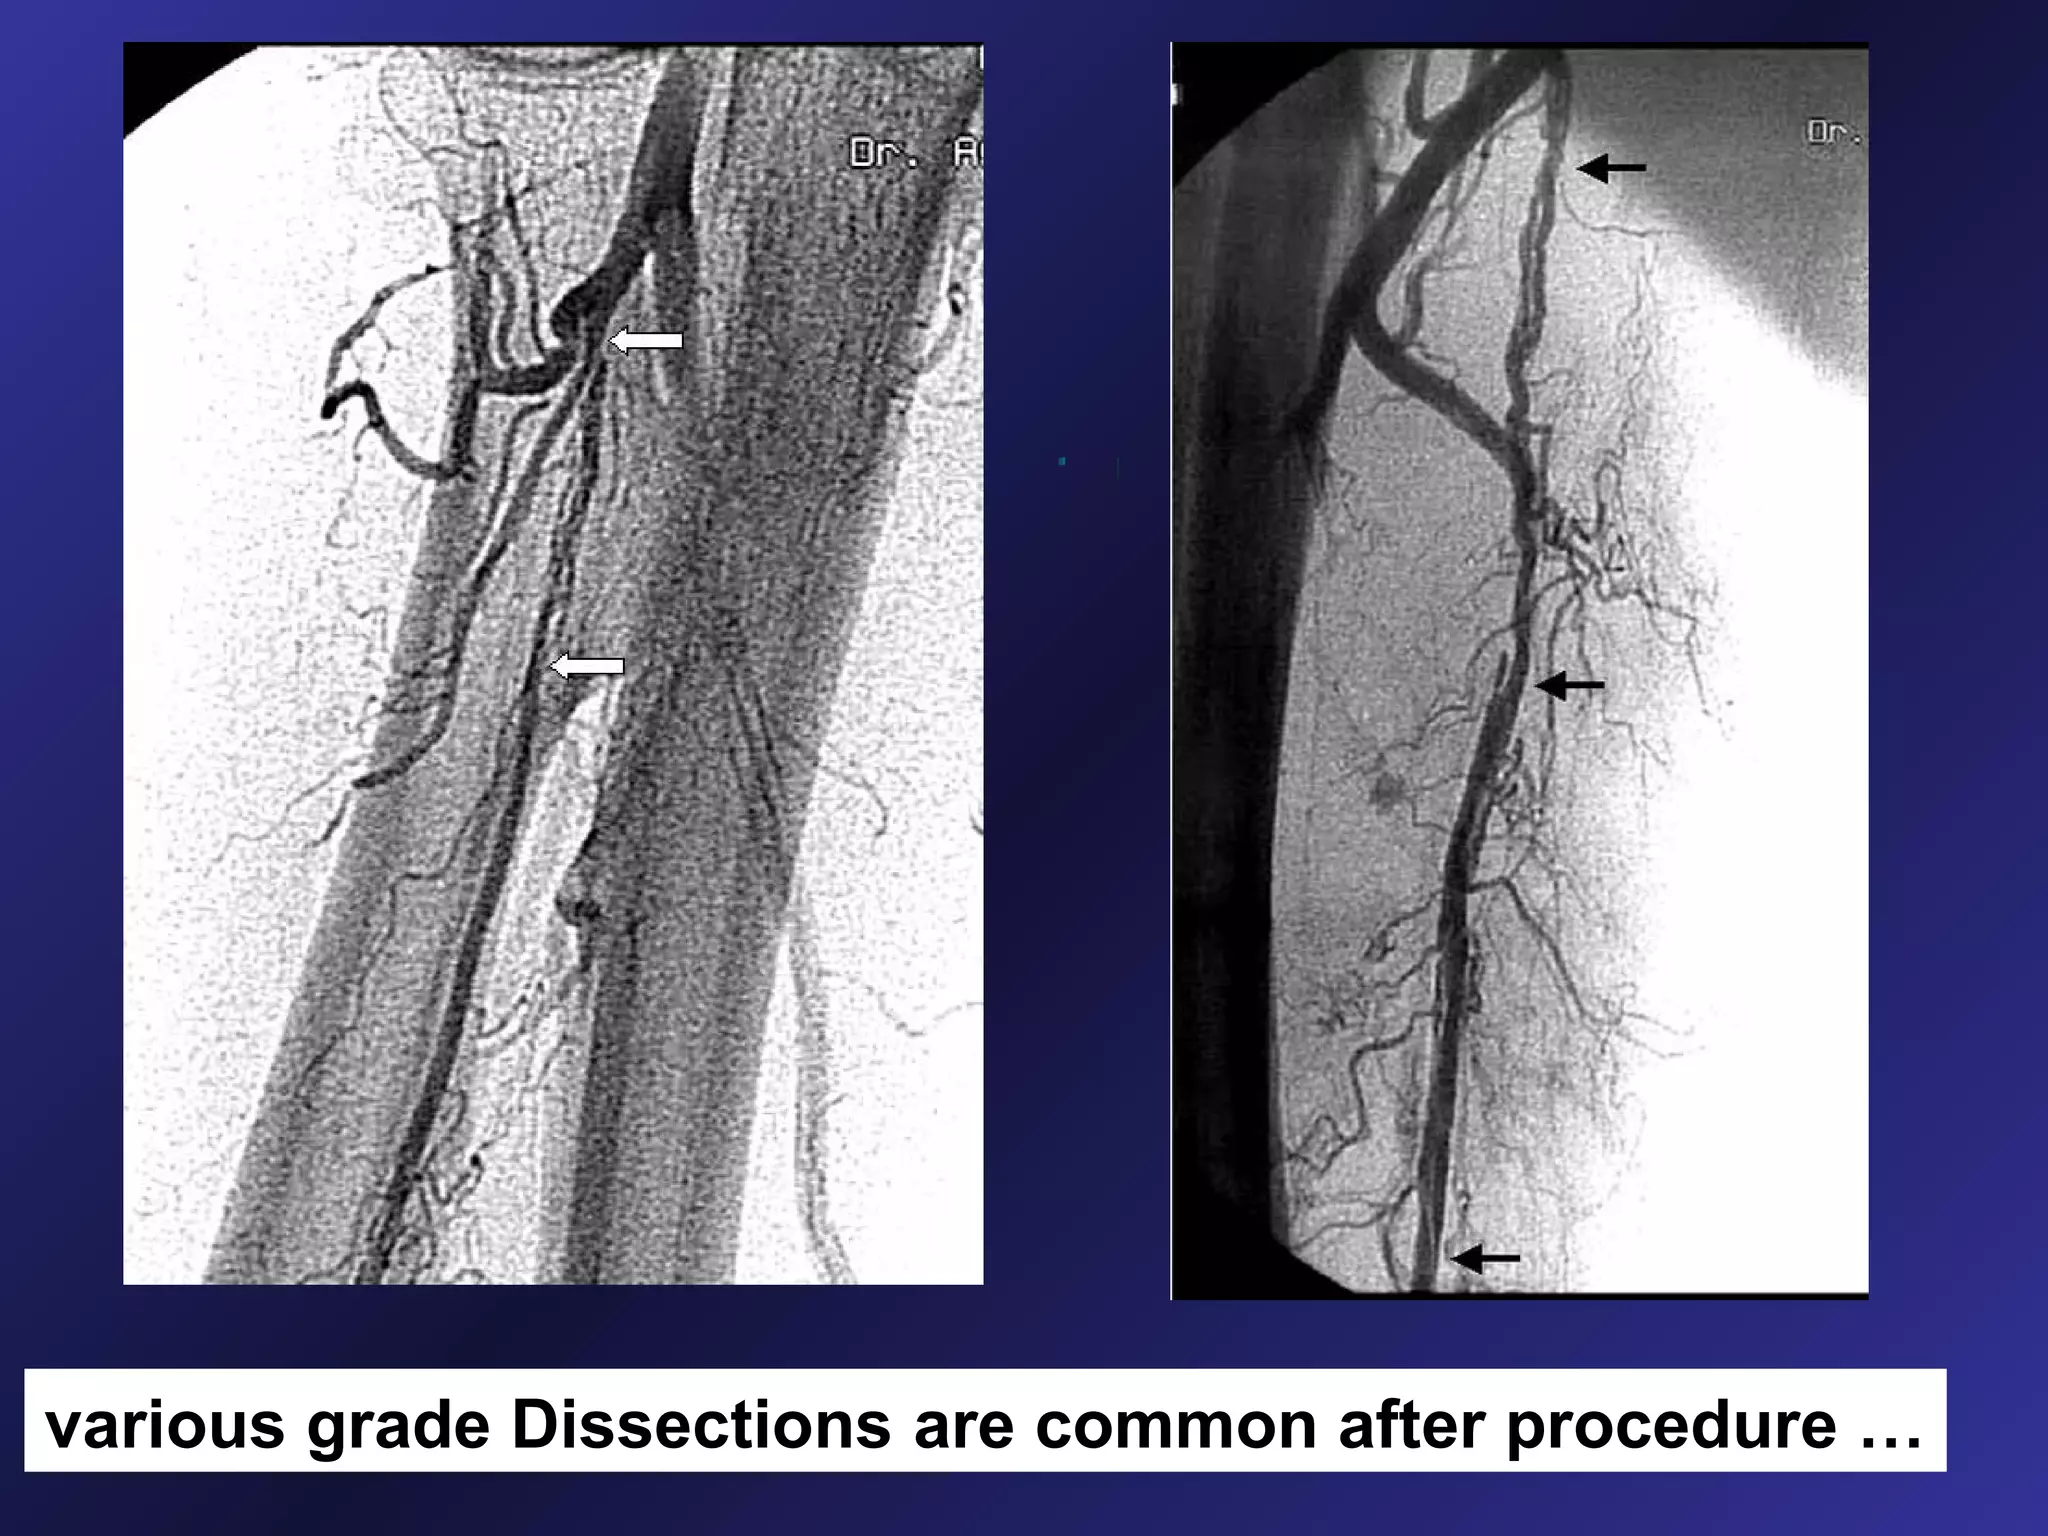

various grade Dissections are common after procedure …

various grade Dissectionsare common after procedure …